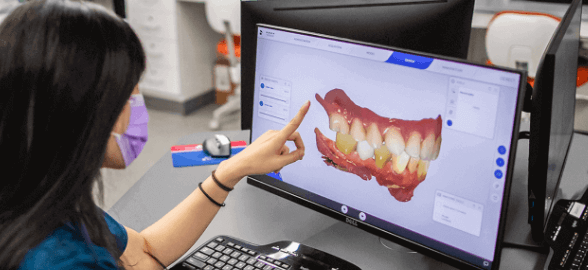

La transformación digital en la odontología no es el futuro, sino el presente.